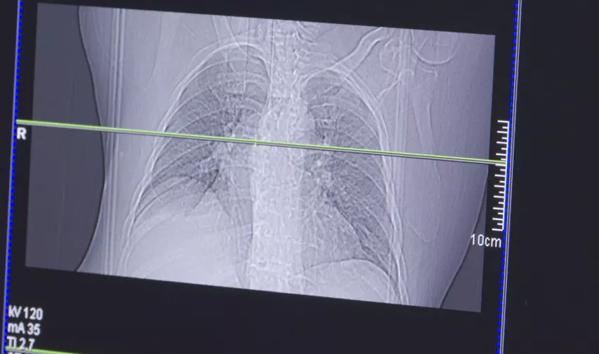

For those unfamiliar, a lung cancer screening is non-invasive and involves a CT scan which creates a detailed X-ray of the lungs.